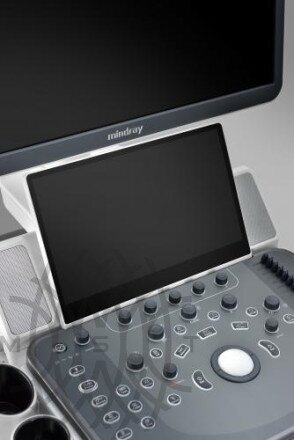

- 23.8" LED монитор высокого разрешения

- Командный сенсорный экран 13.3 дюйма, с технологией распознавания жестов и регулируемым углом наклона

- 23.8" LED монитор высокого разрешения

- Командный сенсорный экран 13.3 дюйма, с технологией распознавания жестов и регулируемым углом наклона